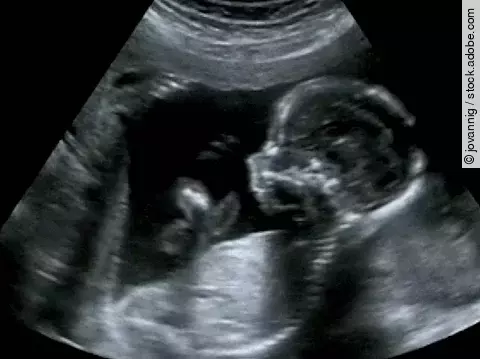

Kommentare jetzt einsendenS3-Leitlinie-Konsultationsfassung: Fetale Überwachung

Diese Leitlinie gilt für alle Berufsgruppen, die Schwangere betreuen und in der Schwangerschaft eine fetale Zustandsdiagnostik durchführen. Das Ziel dieser LL ist die Etablierung der Evidenz dafür, ob in einem low-risk Schwangerschafts-Kollektiv die Durchführung des Dopplers oder CTGs das outcome verbessert.